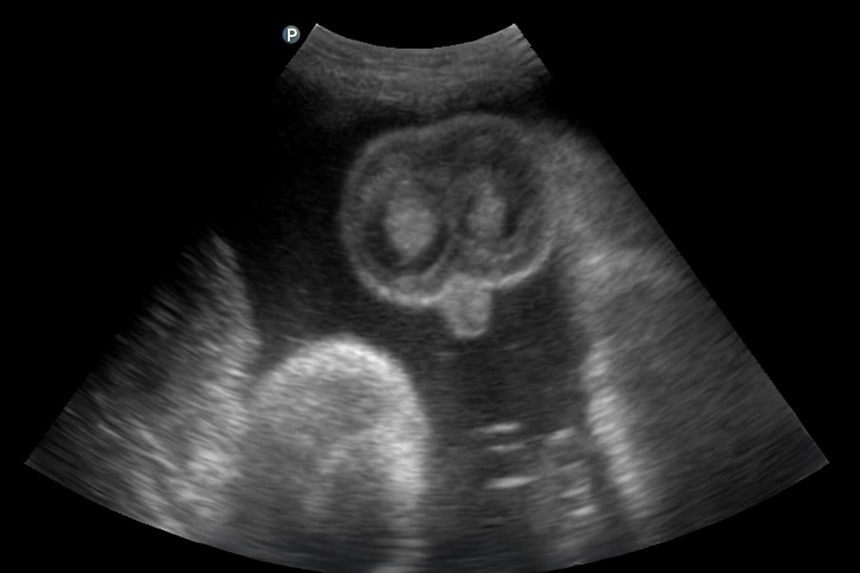

Alle botten in het lijf van je kindje worden steeds harder, zo ook de schedel. De schedel bestaat uit verschillende onderdelen, waartussen zich naden bevinden. Deze groeien nog niet dicht. Dat is maar goed ook, want tijdens de geboorte kunnen de schedelvlakken over elkaar schuiven zodat het hoofdje door het geboortekanaal past. De kans is nu – bij pakweg 32 weken – al vrij groot dat het kindje al met zijn of haar hoofdje naar beneden ligt. De kans op draaien wordt al wat kleiner. Wel kunnen ze tot het einde van de zwangerschap nog met hun rug van links naar rechts draaien. Dat maakt ook niks uit. De positie van het hoofdje in je bekken is nu nog niet van belang. Pas tijdens de bevalling (wanneer er ontsluiting komt) kan het hoofdje verder indalen in je bekken en wordt het belangrijk welke kant het hoofdje op gaat draaien. Die draai (de zogenaamde spildraai) kunnen ze nog heel lang maken; zelfs nog tijdens het laatste deel van de bevalling. In onze module over bevallen laten we dit graag aan je zien!

Het is nu ook belangrijk dat het kindje met het hoofdje naar beneden ligt. Als het uitwendig niet met zekerheid te voelen is, wordt om deze reden een echo gemaakt. Ligt het kindje niet met het hoofdje naar beneden, dan kun je een zogenaamde uitwendige versie laten uitvoeren. Hierbij wordt geprobeerd het kindje te draaien. Als je dit niet wilt of de versie lukt niet, zal er gesproken worden over de opties bij een stuitligging. Alle ins en out die komen kijken bij stuitligging komen aan bod in onze cursus. In een speciale bonusmodule leggen we je alles uit over (verschillende soorten) stuitligging, een versie en de verschillende manieren van geboorte met de voor- en nadelen.